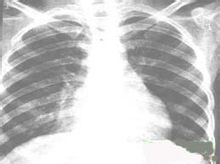

慢性肺炎的特點是周期性的復發和惡化,呈波浪型經過。由於病變的時期、年齡和個體的不同,症狀多種多樣。在靜止期體溫正常,無明顯體徵,幾乎沒有咳嗽,但在跑步和上樓時容易氣喘。在惡化期常伴有肺功能不全,出現發紺和呼吸困難,並由於肺活量和呼吸儲備減少及屏氣時間縮短等,引起過度通氣的外呼吸功能障礙。惡化後好轉很緩慢,經常咳痰,甚至出現面部浮腫、發紺、胸廓變形和杵狀指、趾。由於肺氣腫、肺功能不全而引起肺循環阻力增高,肺動脈壓力增高,右心負擔加重,可在半年至兩年內發生肺原性心臟病。還可能有肝功能障礙。白細胞增加,血沉中度增快。 X線胸片顯示在兩肺中下野及肺門區肺紋理可呈蜂窩狀,出現小泡性肺氣腫,同時還可伴有實質性炎症病灶。兩側肺門陰影可見對稱性增大。隨病變的發展還可發生支氣管擴張、右心室肥大及肺動脈段突出等肺原性心臟病的X線徵象。有肺原性心臟病時,心電圖表現順鐘向轉位,P波高而尖,QRS綜合波多數出現右心室肥厚圖型等改變。